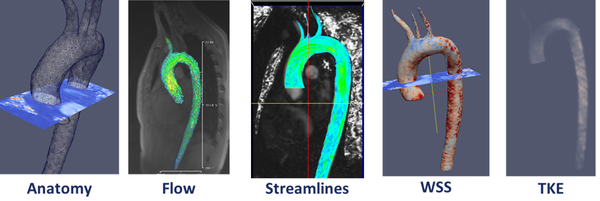

1.4.1.1 4D flow cardiovascular magnetic resonance imaging

At present, 4D flow cardiovascular magnetic resonance imaging (4D CMRI) sequences are being a promising tool to visualize and quantify 4D (3D+t) blood flow. From these sequences the raw data can be obtained and conveniently processed, allowing visualization of the blood flow patterns in any segment of the cardiovascular tree[71][72][73]. Nevertheless, the visualization of these images entails an important manual work, becoming a very time-dependent task and then turning out to be not useful in the current clinical practice. Therefore, it is important to improve the technology and the methods of automatic representation of the 4D blood flows, in particular for the WSS analysis. In chapter 5, it is demonstrated that 4D flow CMRI technique is a reliable tool to provide the boundary conditions for the Computational Fluid Dynamics(CFD) in order to estimate the WSS within the entire thoracic aorta in a short computation time. Our image-based CFD methodology exploits the morphological MRI for geometry modelling and 4D flow CMRI for setting the boundary conditions for the fluid dynamics modelling. The aim is to evaluate visualization of well-defined aortic blood flow features and the associated wall shear stress by the combination of both techniques. In that sense, CIMNE has developed a home-made ad-hoc software (Aorta4D) oriented to make progress in this field of work [72][74][73]. Aorta4D will afford analysis and spatially visualization of the registered 3-directional blood flow velocities, and perform a 3D semi-automatic segmentation based on the 4D flow CMRI data.

Scientific contribution: Designed new methodology to estimate the Wall Shear Stress(WSS) using 4D flow cardiovascular MR data and computational fluid dynamics. The methodology proposed is based on interpolate the data acquired from the 4D flow CMR sequence into a patient-specific refined-mesh computational mesh. This paper is a proof-of-concept to validate WSS using CFD data.

Contribution to the paper: This work is being carried out in collaboration with the E.T.S. d'Enginyeries Industrial i Aeronáutica de Terrassa (ETSEIAT), UPC and the Unidad de Imagen Cardiaca, Servicio de Cardiología, Hospital de la Santa Creu i Sant Pau. The simulation in the OPENFOAM software([88]) was performed during the final career project of Jordi Casacuberta in the ETSEIAT. The author of this monograph has developed the algorithm and the methodology for the calculation of the WSS using 4D flow CMR data in collaboration with Jorge S.Pérez (CIMNE). The author of this monograph has also contributed in the segmentation and the analysis of results.

In this monograph we have developed a geometrical multiscale framework for simulation cardiovascular diseases under different physiological and pathological conditions. The cardiovascular diseases studied under this multiscale framework were the Aorta Coartaction and Coronary Disease, but, the technology underlying is applicable to other common cardiovascular conditions, including peripheral, cerebrovascular, and reno-vascular disease, and may be used to determine whether vascular stenosis are hemodynamically significant as well as the relative benefit of therapeutic interventions. In this line, we have also proposed a new coronary indicator to evaluate the stenosis without hyperemia condition (under evaluation). At the same time, we have developed and validated a 1D numerical model coupled with the reduced order model. A 1D-reduced order model validation for other groups of people or patients could also be useful for research and clinical outcome analysis. The 1D model is able to describe the pulse wave dynamics and the interaction between the heart and the circulatory system. We have also studied the hemodynamics factors that may be important in triggering the onset of aneurysms correlated with the patient-specific anatomy. The hemodynamics factor and the geometry are directly related with the ILT formation. More AAA cases are needed to define a direct correlation between the hemodynamics factors and AAA development. Quantification of WSS, as well as other WSS-based indicators, are of crucial importance for the understanding of the development of cardiovascular pathologies as, aneurysm or arteriosclerosis. In this way, the feasibility of CFD as a predictive tool to use for treatment planning of cardiovascular diseases has been demonstrated. A methodology to obtain computational meshes from medical image has been defined. A new procedure to segment the aorta using 4D flow CMR data has also been proposed. Beyond this, 4D flow CMR visualization offers a more qualitative and comprehensive description of the flow fields than any other in-vivo imaging technique. The velocity data provided by 4D flow CMR has been complementary to the higher resolution velocity fields computed by the CFD in order to estimate the WSS. We have also developed an algorithm to compute WSS based on the 4D flow CMR data. Based on that approach other diagnostic indicators could be estimated, as pulse wave velocity(PWV)[89], turbulent kinetic energy[90], relative pressure fields[91] or volume and kinetic energy of ventricular flow compartments[92]. For full details refer to the 'Results sections of papers.